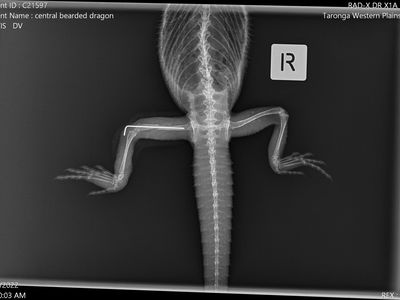

The Wildlife Hospital located at Taronga Western Plains Zoo cares for not only the animals at the zoo but also sick and injured wildlife that come into the zoo as a result of events such as natural disasters. The hospitals located in Dubbo and at Taronga Zoo in Sydney see close to 1,500 wildlife cases each year.

Opened in December 2022, the new Wildlife Hospital provides a literal window into the work of the Zoo’s vets and conservation scientists, letting guests see this life saving work for themselves.